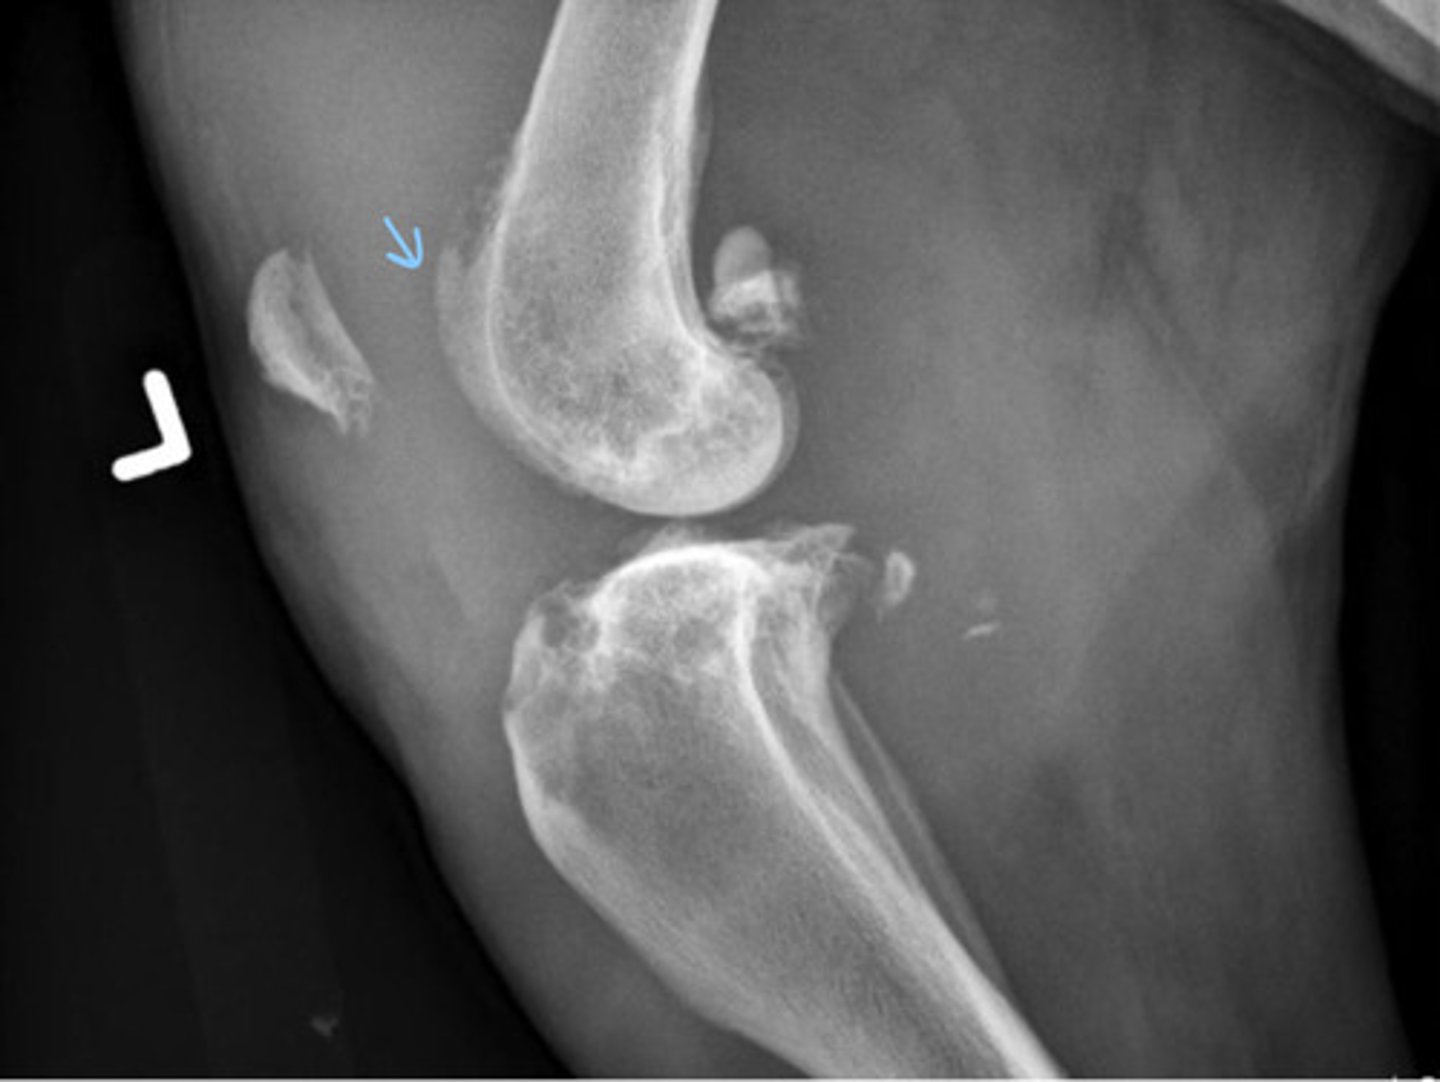

Synovial cell neoplasia

What does this patient have?